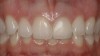

The final screw-retained crown was delivered and torqued onto the implant to 35 Ncm; the restorative dentist then sealed the screw access with a cotton pellet and composite (Figure 20 and Figure 21). Various views of the final crown are shown in Figure 22 through Figure 25, including a full-face photograph.

This patient faced a unique situation, perhaps not previously reported: retaining a healthy mandibular lateral incisor knowing this would create an esthetic compromise. Indeed, while the discrepancy in gingival-margin height is noticeable in retracted view (Figure 7), it does not show in full smile (Figure 8).

The gingival frame of the final implant crown on tooth No. 9 successfully matched that of natural tooth No. 8 (Figure 23). Accomplishing this required not only preservation of the existing free-margin height, but also the mirroring of the zenith point (at the approximate junction of the middle and distal thirds of each incisor’s clinical crown).

Figure 20  Screw-retained zirconia crown, customized zirconia stock abutment (one-piece restoration), site No. 9—final periapical view.

Figure 20

Figure 21  Screw access of final zirconia crown sealed with composite resin—incisal view.

Figure 21